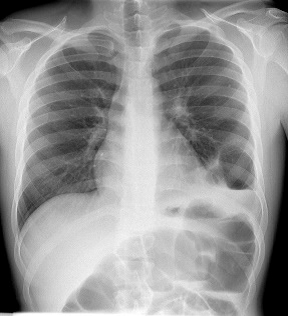

(SES-PE 2018.2 ACESSO DIRETO) - Paciente vítima de acidente motociclístico em alta velocidade. Conduzido à emergência em estado grave, hipotenso e dispneico. Realizou o RX tórax abaixo. Qual é o diagnóstico provável?

A) Hérnia diafragmática E

B) Pneumotórax D e Hemotórax E

C) Hemotórax E

D) Pneumotórax E

E) Tamponamento cardíaco

Letra “A” - Hérnia diafragmática E